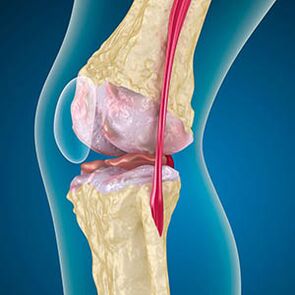

Con la artrosis, el cartílago que recubre los bordes de los huesos es abrasión o completamente ausente. El tejido dañado no es una fuente de dolor, porque no tiene receptores. La inflamación en las estructuras cercanas causa síntomas característicos.

El cuerpo continúa la regeneración de tejidos dañados, pero el cartílago crece de manera desigual. Como resultado, se forman irregularidades que dañan otros elementos de la articulación. La naturaleza de los osteófitos se explica por la compensación para el cartílago de articulaciones lisas. Otra versión indica que el crecimiento de "espuelas" Se asocia con un intento de estabilizar la articulación medial o lateral debido al debilitamiento muscular.

La hinchazón es causada por una lesión en tejidos blandos, inflamación de los tendones y la bolsa articular. La aparición de calor en la rodilla, la hinchazón indica la acumulación de exudado inflamatorio -La artrosis a menudo se acompaña de bursitis, sinovitas, tendinitis.

El crujido en la rodilla es indoloro y traumático. Los tintineo y otros sonidos no dicen que los huesos son abrasión. Signos de violación de la estabilidad de la rodilla - La debilidad de uno del control de los músculos.

La credación causada por la fricción del hueso en el hueso no ocurre al principio y al final de la amplitud del movimiento, sino en el medio, Incluso con flexión pasiva de la articulación. El bloqueo de la articulación es causado por el desgaste del cartílago y los tendones, lo que crea una sensación de fijación. Los huesos con cualquier movimiento están controlados por los músculos. Su reducción inoportuna conduce a una dirección cambiada del movimiento óseo, bloqueando.